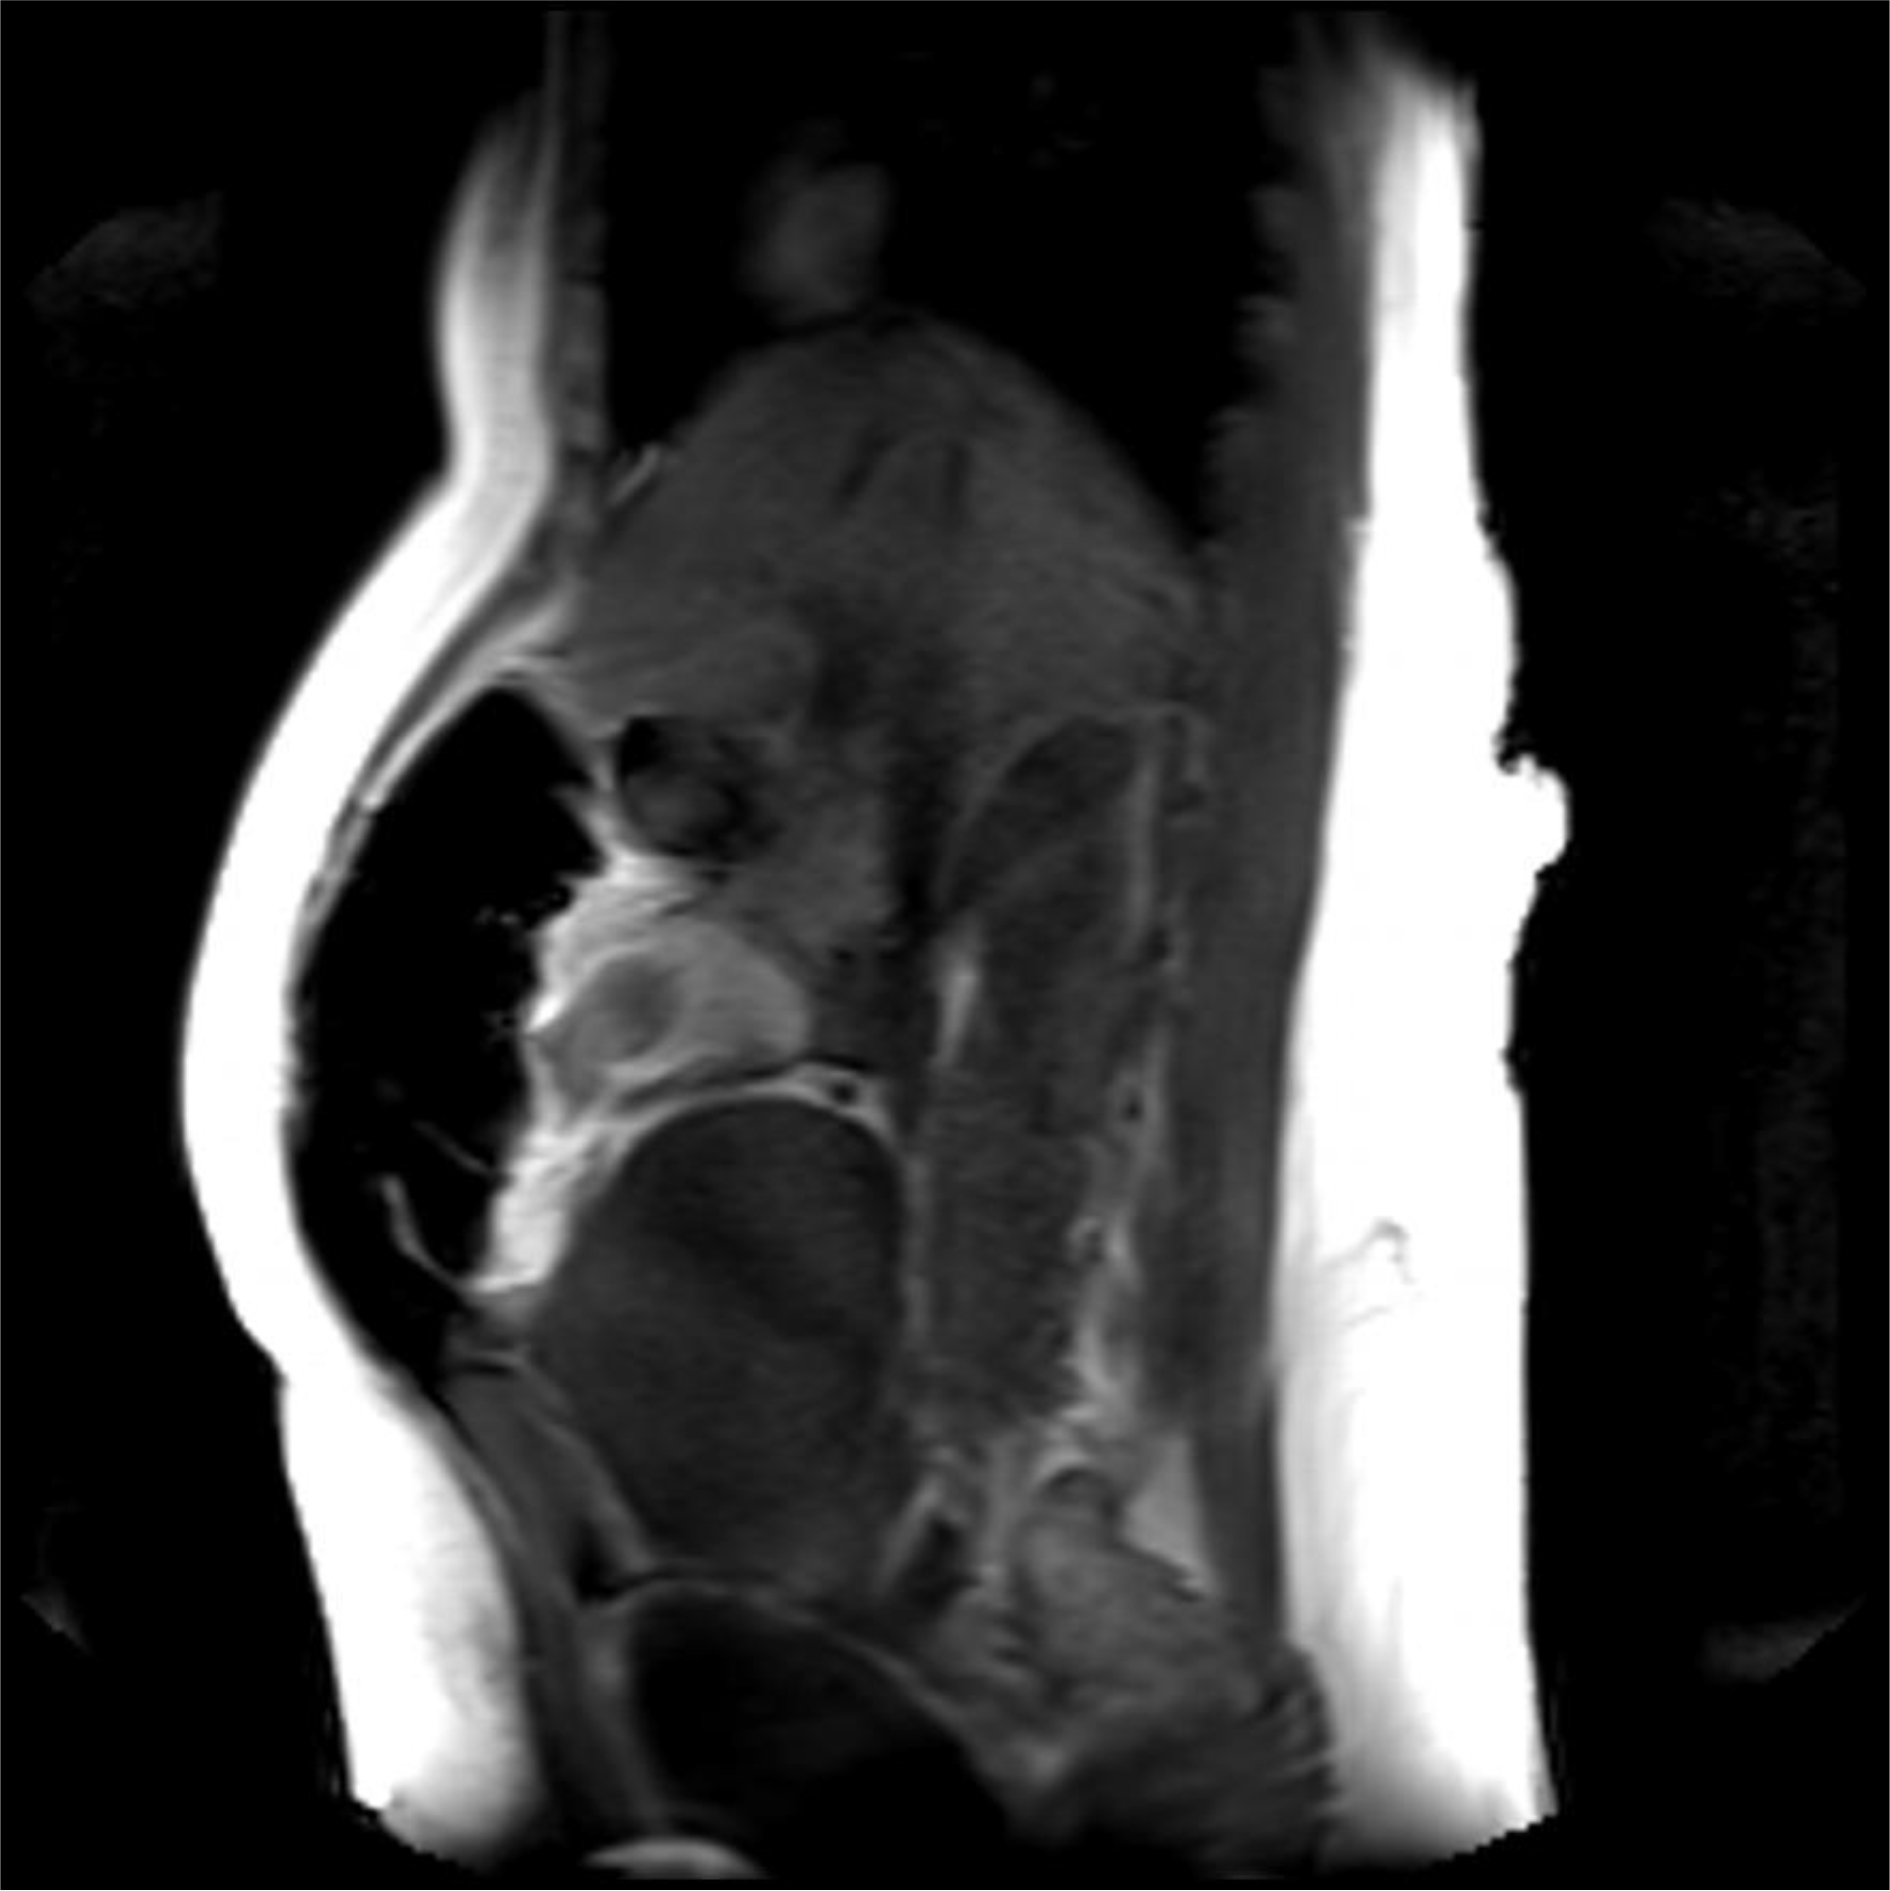

A magnetic resonance imaging (MRI) image of the uterus was given in two cases as an example of the groups that did not apply sandbags (Fig. 2) and that did (Fig. 3).

Fig. 2.Postoperative 4th hour magnetic resonance imaging (MRI) image of a patient who did not apply sandbag. It shows the uterus contracting and the anteflexio position of the uterus.

In our study, as a second theory, we thought that by applying external pressure to the uterus, bleeding after CS could be reduced. Namely, uterine massage [35] aiming to provide contraction of the uterus with fundus pressure, uterine balloon tamponade methods aiming to stop bleeding by applying internal pressure to the uterus [36, 37], uterine compression sutures that are reported to provide hemostasis with 90% success by shrinking the uterine cavity as in bimanual uterine compression (B-Lynch, Hayman, Pereira, Square suture, U sutures, Matsubara, etc.) [38]. Some of the above-mentioned methods are effective in reducing postpartum uterine bleeding by applying pressure to the uterus from the inside, some from the outside and shrinking the uterine cavity. Based on this pressure effect, we investigated its effectiveness as a method for reducing the amount of bleeding after CS by applying abdominal fundal pressure to the uterus in the first 6 hours postpartum. As a result of our study, the amount of bleeding was statistically significantly higher than in our control group. However, when we evaluated it clinically, there was no difference in terms of anemia. In our opinion, the sandbag left on the uterine fundus disrupted the anteflexion position of the uterus and brought it to the extension position. We obtained information about the position of the uterus by magnetic resonance imaging (MRI) in some of our patients who had and did not apply sandbags. As a result of MRI, we observed that the uterus lengthened towards the umbilicus and the anteflexion position was impaired, as if the uterus was in atony in the weight-applied group. According to the results of our study, sandbag application does not seem to reduce bleeding after CS. However, sandbag application may be beneficial in preventing complications such as incision bleeding, hematomas or rectus hematoma formation due to the local pressure effect on the skin and subcutaneous tissues. However, in our study cutaneous, subcutaneous or rectus hematoma was not observed in any of our patients in either group we could not comment on this issue.

In cases where we did not apply weight, we experienced that the uterus contracted like a fist. Our MRI findings showed that weight application could not have a positive effect on uterine contractions contrary to our previous thought. This position disorder and continuous pressure effect in the uterus disrupted the synchronization of uterine contractions and was not effective in reducing bleeding. Because if we think like the B-Lynch effect, while the anteflexion position of the uterus reduces bleeding, we have disrupted this position with a sandbag. Disruption of the postpartum position of the uterus may have caused dysfunction in the contraction of the spiral arteries by the myometrium by disrupting the contraction pattern of the myometrium, or it may have created a trauma effect [23, 24]. In addition, the sandbag may have caused myometrial muscle fatigue by encouraging continuous contraction of the myometrium due to uterine pressure. Zhao et al. [39] used a multifunctional airbag abdominal compression belt in the second and third stages of labor in a study. As a result of the study, the internal pressure of the belt was closely monitored and appropriately adjusted to the patient. It has been reported that the multifunctional airbag abdominal compression belt can accelerate the second and third stages of labor, prevent postpartum hemorrhage and promote natural birth. The sandbag we used in our study can look like to the multifunctional airbag abdominal pressure belt. Because the purpose of both is to apply pressure to the uterine fundus. However, the multifunctional airbag abdominal compression belt has been used to facilitate childbirth. Pressure adjustment control has also been made in this belt. Pressure setting control can be very important during labor. Because there is a fetus that may be at risk. This pressure setting can also be lowered if the fetus is in distress during delivery. However, in our sandbag application, there is no controlled pressure setting, it presses the fundus as much as the weight of the sandbag. However, since we apply the sandbag after birth, we will not have a problem such as fetal distress. As a result, it is similar to our study that the described belt application has been shown to reduce the amount of postpartum hemorrhage as well as facilitating childbirth. However, we showed that sandbag application did not reduce the amount of postpartum bleeding. The reason for this difference may be due to the fact that the belt is more applicable and pressure-adjusted and was applied during delivery. In addition, sandbag application can be considered as a primitive method. However, our sandbag application can apply uterine pressure from the abdomen in non-invasive ways and can give an idea about the construction of pressure-adjusted compressor devices.